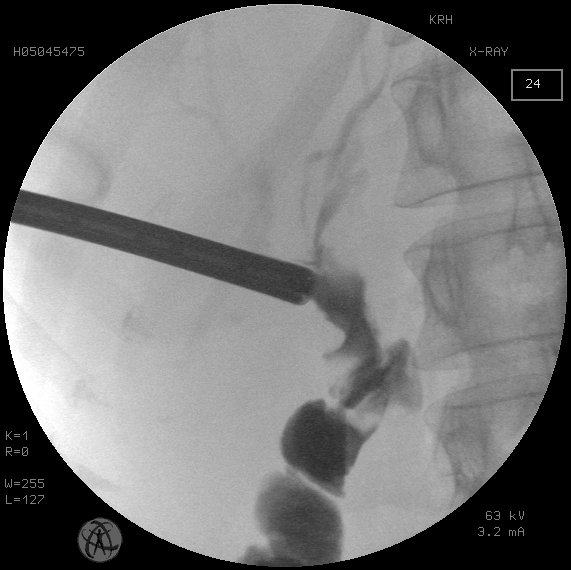

Рис. 2. То же наблюдение, состояние после чреспеченочной холангиостомии большого диаметра и частичной литотрипсии

Fig. 2. The same observation. Сondition after large-diameter transhepatic cholangiostomy and partial lithotripsy

Группу исследования составили 16 пациентов со стриктурами БДА, осложненными холелитиазом. В трех случаях удалось низвести конкременты общего печеночного протока в отводящую кишку после баллонной дилятации стриктуры БДА. В 13 наблюдениях при мегахолелитиазе потребовалась этапная модификация пункционного холангиостомического доступа в чрескожный рентгенохирургический доступ диаметром 9 мм для последующей контактной механической и пневматической литотрипсии и литоэкстракции (рис. 1–5).

Случаи сочетания рубцовой стриктуры БДА с холелитиазом рассматриваются отдельно. Традиционно холелитиаз, осложняющий стриктуру БДА, рассматривается как фактор, предполагающий хирургическую реконструкцию анастомоза. Тем не менее необходимо отметить, что факт наличия конкрементов проксимальнее зоны БДА еще не является основанием для безусловного отказа от использования рентгенохирургических методик разрешения холелитиаза. Как показали результаты использования антеградного чреспеченочного доступа в желчное дерево с последующей контактной литотрипсией у пациентов группы исследования, полное освобождение желчного дерева от конкрементов было достигнуто у всех больных. При этом использовалась экстремальная модификация первичного холангиостомического доступа до 30 Fr для последующих внутрипротоковых манипуляций с ригидным перкутанным нефроскопом под операционный кожух 24, 26 СН с контактной пневматической литотрипсией (см. рис. 1–5). Такая методика используется нами более 20 лет и зарекомендовала себя не только эффективной, но и безопасной при условии бесконфликтности первичной чреспеченочной пункции желчного дерева [Охотников и др., 2011; Охотников и др., 2012].